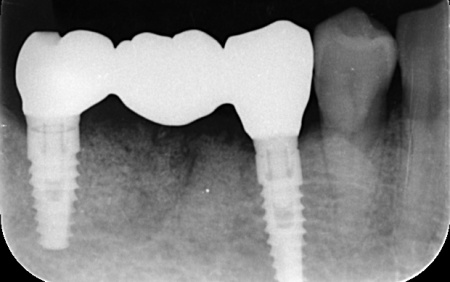

| カウンセリング | 拝見したところ、右下奥歯2本が噛むと痛む状態でした。 これらの歯は、以前神経を除去する処置を行っており、その後銀歯にされていたとのことです。 詳しく調べるためにレントゲン撮影を行った結果、どちらの歯も歯根が割れていることが確認できました。 歯根が割れた歯は元の状態に戻すことができず、そのまま放置すると炎症が広がって周囲の骨や隣接する歯に悪影響を及ぼすリスクがあります。 以上のことから、抜歯をしたうえで歯を補う治療が必要だと診断しました。 |

①入れ歯 ②インプラント それぞれのメリットとデメリットをお伝えしたところ、患者様は「できるだけ違和感がなく噛めるようになりたい。またなるべく短期間で治療を終えたい」と希望されたため、抜歯と同時にインプラントを埋め込む抜歯即時埋入法を提案し、同意いただきました。 まず、右下奥歯(第2小臼歯、第1大臼歯)を抜きます。 抜歯後にできた穴とインプラントの間には隙間が生じるため、骨の再生を助ける目的で骨補填材を使用しながら、丁寧に縫合しました。 3ヶ月後、インプラントと骨がしっかりと結合したことが確認できたため、被せ物を作製するための型取りを行います。 後日、完成した被せ物を装着し、見た目や噛み合わせに問題がないことを確認して、治療を終了しています。 |